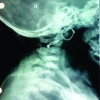

He sustained an open 3A comminuted right PPF with his clothing contaminating the fracture site (Fig. 2). The open wound was present on the anterior aspect of his thigh (Fig. 3). His PPF was classified as VTB2W with no evidence of loosening at the cement bone interface (Fig. 4).

Although PPF is common, open PPF is extremely rare. We present a rare case of a 74-year-old gentleman who sustained a traumatic Gustillo-Anderson grade 3A VTB2W fracture which had an ORIF with a double plate with supplementary cable fixation. He had a fully cemented primary right THA in the Exeter Hip Unit, United Kingdom 7 years before his PPF for primary hip osteoarthritis (Fig. 1).